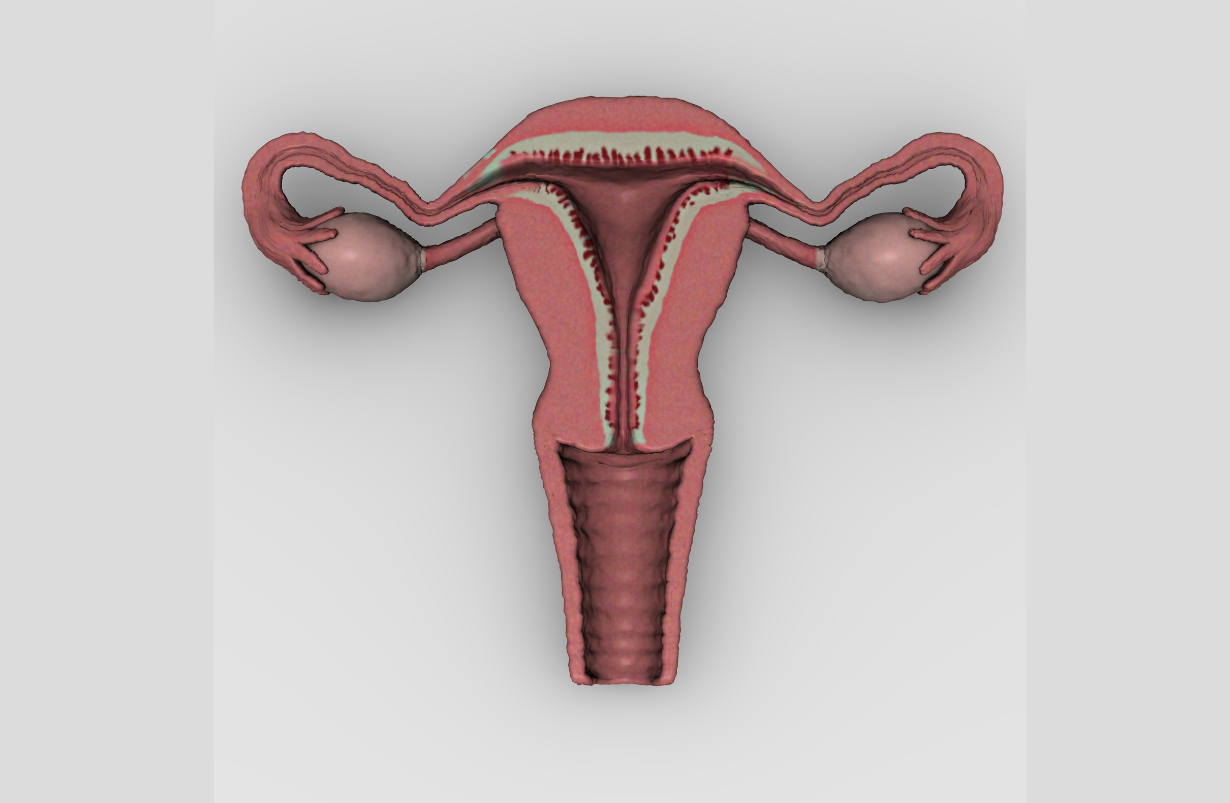

Endometriosis

Endometriosis involves the growth of uterine-like tissue within the ovaries, fallopian tubes, and elswwhere in the pelvis. It is often painful.

Menstruation

Tissue gathered in the uterus to receive a fertilized egg is sloughed in the process of menstruation if no fertilized egg is present. It is not a medical condition but a normal recurrent episode lasting approximately 4-5 days of each 28 day cycle. However, it is often accompanied by cramps. The poses below are suggested as beneficial for those women suffering menstrual cramps. However, very vigorous exercise is noted to stimulate anti-menstrual hormones and is best avoided during this phase of the ovulatory cycle. BENEFICIAL POSES: Baddha Konasana, Dhanurasana, Utthita Parsvakonasana, Ardha Matsyendrasana I. EXPLANATION: Changes in genital tissue volume and fluid accumulations in the abdominal cavity may produce muscle spasm. These poses stretch most of the muscles that are likely to be involved, an put mild pressure on the abdominal cavity that can prompt reduction in its fluid content. Contraction of ligamentous bands in premenstrual syndrome is well-treated with these poses as well. REFERENCES: O'Leary CB1, Lehman C, Koltun K, Smith-Ryan A, Hackney AC.Response of testosterone to prolonged aerobic exercise during different phases of the menstrual cycle.Eur J Appl Physiol. 2013 Sep;113(9):2419-24. doi: 10.1007/s00421-013-2680-1. Epub 2013 Jun 28. Amanda Daley. The role of exercise in the treatment of menstrual disorders: the evidenceBr J Gen Pract. 2009 Apr 1; 59(561): 241–242.doi: 10.3399/bjgp09X420301 PMCID: PMC2662100PMID: 19341553. Yang NY, Kim SD. Effects of a Yoga Program on Menstrual Cramps and Menstrual Distress in Undergraduate Students with Primary Dysmenorrhea: A Single-Blind, Randomized Controlled Trial. J Altern Complement Med. 2016 Sep;22(9):732-8. doi: 10.1089/acm.2016.0058. Epub 2016 Jun 17.

Pregnancy (second and third trimesters)

Usually divided into three month trimesters. These contraindications apply only in the second and third trimesters, when the placenta is larger. One of the chief worries is that twisting will separate some of the placental tissue from the uterus. BENEFICIAL POSES: Upavista Konasana, Baddha Konasana, Gomukhasana, Garudasana, Leaning. EXPLANATION: The uterus is held in place by six paired ligaments, the uterosacral, the cardinal, broad, round, ovarial, and indirectly, the ovarian suspension ligaments. Twists tighten one of each ligament pair, asymmetrically tugging the gravid uterus to one side, producing shearing forces that may dislodge some or all of the placenta. However, symmetrical poses of moderate intensity that elongate and promote control of adductors, such as Upavista Konasana and Baddha Konasana are recommended. Toward the middle of pregnancy, the placenta begins to secrete the hormone relaxin, which, as the name suggests, relaxes many ligaments, allowing the uterus to grow exponentially and the young one to exit the birth canal. At this point the mother begins to carry a good deal of weight in her abdomen, and puts significant and unfamiliar strain on the sacroiliac joints, the ligaments of which are now too flexible to resist the extra stress. Sacroiliac joint derangement is countered by the series Gomukhasana, Garudasana, and 'Leaning,' the latter pictured in the video below. REFERENCES: Jiang Q, Wu Z, Zhou L, Dunlop J, Chen P. Effects of yoga intervention during pregnancy: a review for current status.Am J Perinatol. 2015 May;32(6):503-14. doi: 10.1055/s-0034-1396701. Epub 2014 Dec 23. Martins RF, Pinto e Silva JL.Treatment of pregnancy-related lumbar and pelvic girdle pain by the yoga method: a randomized controlled study. J Altern Complement Med. 2014 Jan;20(1):24-31. doi: 10.1089/acm.2012.0715. Epub 2013 Mar 18. Fishman, LM. "Healing Yoga - Proven postures to treat twenty common ailments." W.W. Norton and Co. New York: 2014.